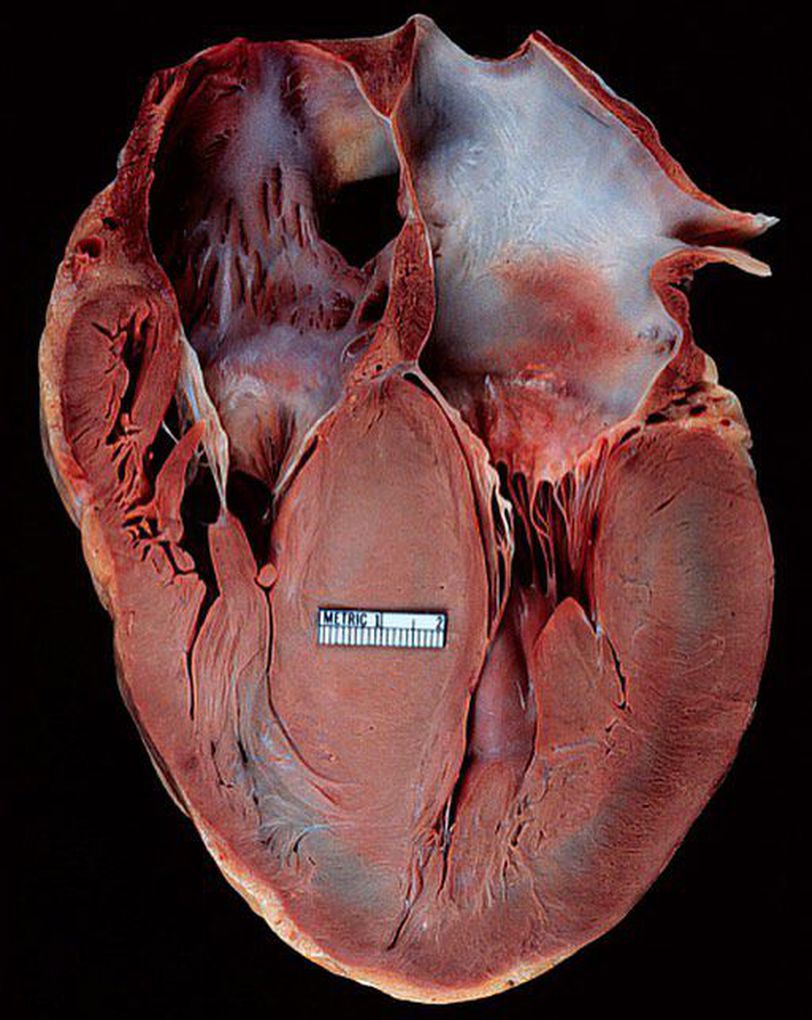

That septum definitely looks thick! Hypertrophic cardiomyopathy is a condition in which the myocardium becomes thickened, making the heart muscle stiff, especially of the septum and ventricles (lower heart chambers), which is seen very clearly in this picture. The pathophysiology behind it is that the sarcomeres (contractile elements) in the heart replicate causing heart muscle cells to increase in size, which results in the thickening of the heart muscle. In addition, the normal alignment of muscle cells is disrupted, a phenomenon known as myocardial disarray. The average left ventricular wall thickness in normal adults is 1.1 cm, but there are exceptions. Trained athletes have hearts that have left ventricular mass up to 60% greater than untrained subjects, with an average left ventricular wall thickness of 1.3 cm. The most common cause is hypertension. As many as 1/3 of patients show left ventricular hypertrophy of any degree along with hypertension. Symptoms are quite variable and range from no symptoms, to the development of heart failure, to the occurrence of sudden cardiac death. Symptoms include dyspnea (shortness of breath) due to stiffening and decreased blood filling of the ventricles, exertional chest pain (angina) due to reduced or restricted blood flow to the coronary arteries, uncomfortable awareness of a fluttering or pounding heart beat (palpitations) due to the ischemia to the heart muscle, disruption of the electrical system running through the abnormal heart muscle, lightheadedness, fatigue, fainting (called syncope) and sudden cardiac death. Treatment goals are to minimize diastolic dysfunction, reducing LV outflow tract obstruction, optimizing heart failure management, maintaining normal sinus rhythm, rate control and anticoagulation in the presence of atrial fibrillation, and implantation of an automatic implantable cardiac defibrillator in those patients who survive sudden cardiac death.

Asymmetrical hypertrophy not like LVH of hypertension which is symmetrical . Another point surgical treatment in severe cases(myectomy) is a very good option in well-recognized cardiac centres.